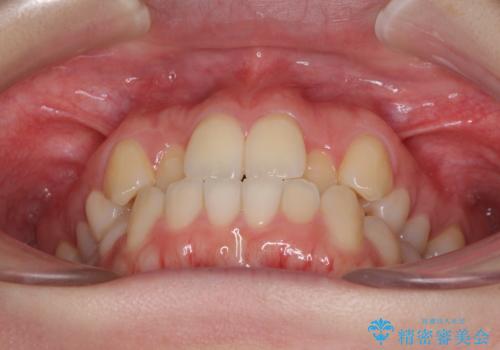

前歯のクロスバイトをインビザライン矯正で改善

- 前歯のデコボコと上下のクロスバイトを気にして来院された患者様です。

インビザラインを用い、IPR(歯と歯の間を削る)と歯列全体を拡大させることで、歯並びを整えていくこととしました。

上の前歯が下の前歯を乗り越える際、奥歯がほとんど咬めない時期があり、乗り越えた後も、インビザライン特有の奥歯の咬みにくさが続きました。

咬み合わせ改善のために治療期間を要しましたが、最終的に奥歯はしっかりと咬めるようになりました。